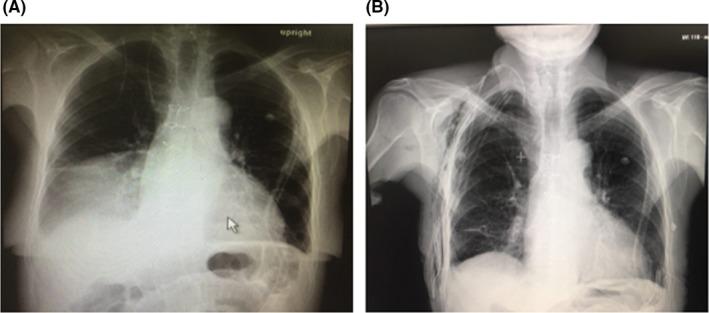

Sigmoid volvulus after CABG surgery.

We report a case of a geriatric patient who underwent CABG and developed sigmoid volvulus (SV) with recurrence. SV is a rarely reported complication of CABG. Timely diagnosis, management, and follow-up are strictly advised, particularly in geriatric patients. Immediate surgical measures are required to prevent volvulus-associated ischemia.